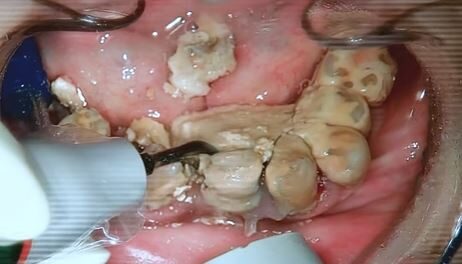

一位牙醫師陳煥鈞最近在臉書粉絲專頁公開了一段令人震驚的診療過程,畫面中他從病患嘴裡清除出一塊體積驚人的牙結石,尺寸竟然達到11mm之大!這個誇張的數字讓陳醫師都忍不住感嘆,這絕對是他執業以來遇過最巨大的牙結石案例。

影片一曝光就在網路上掀起熱烈討論,許多網友看到這驚悚的畫面都嚇傻了,紛紛留言追問:「這個人究竟多久沒有洗牙或刷牙了?」面對大家的好奇,陳醫師相當淡定地給出答案:「10幾年。」這個回答讓眾人更加傻眼。